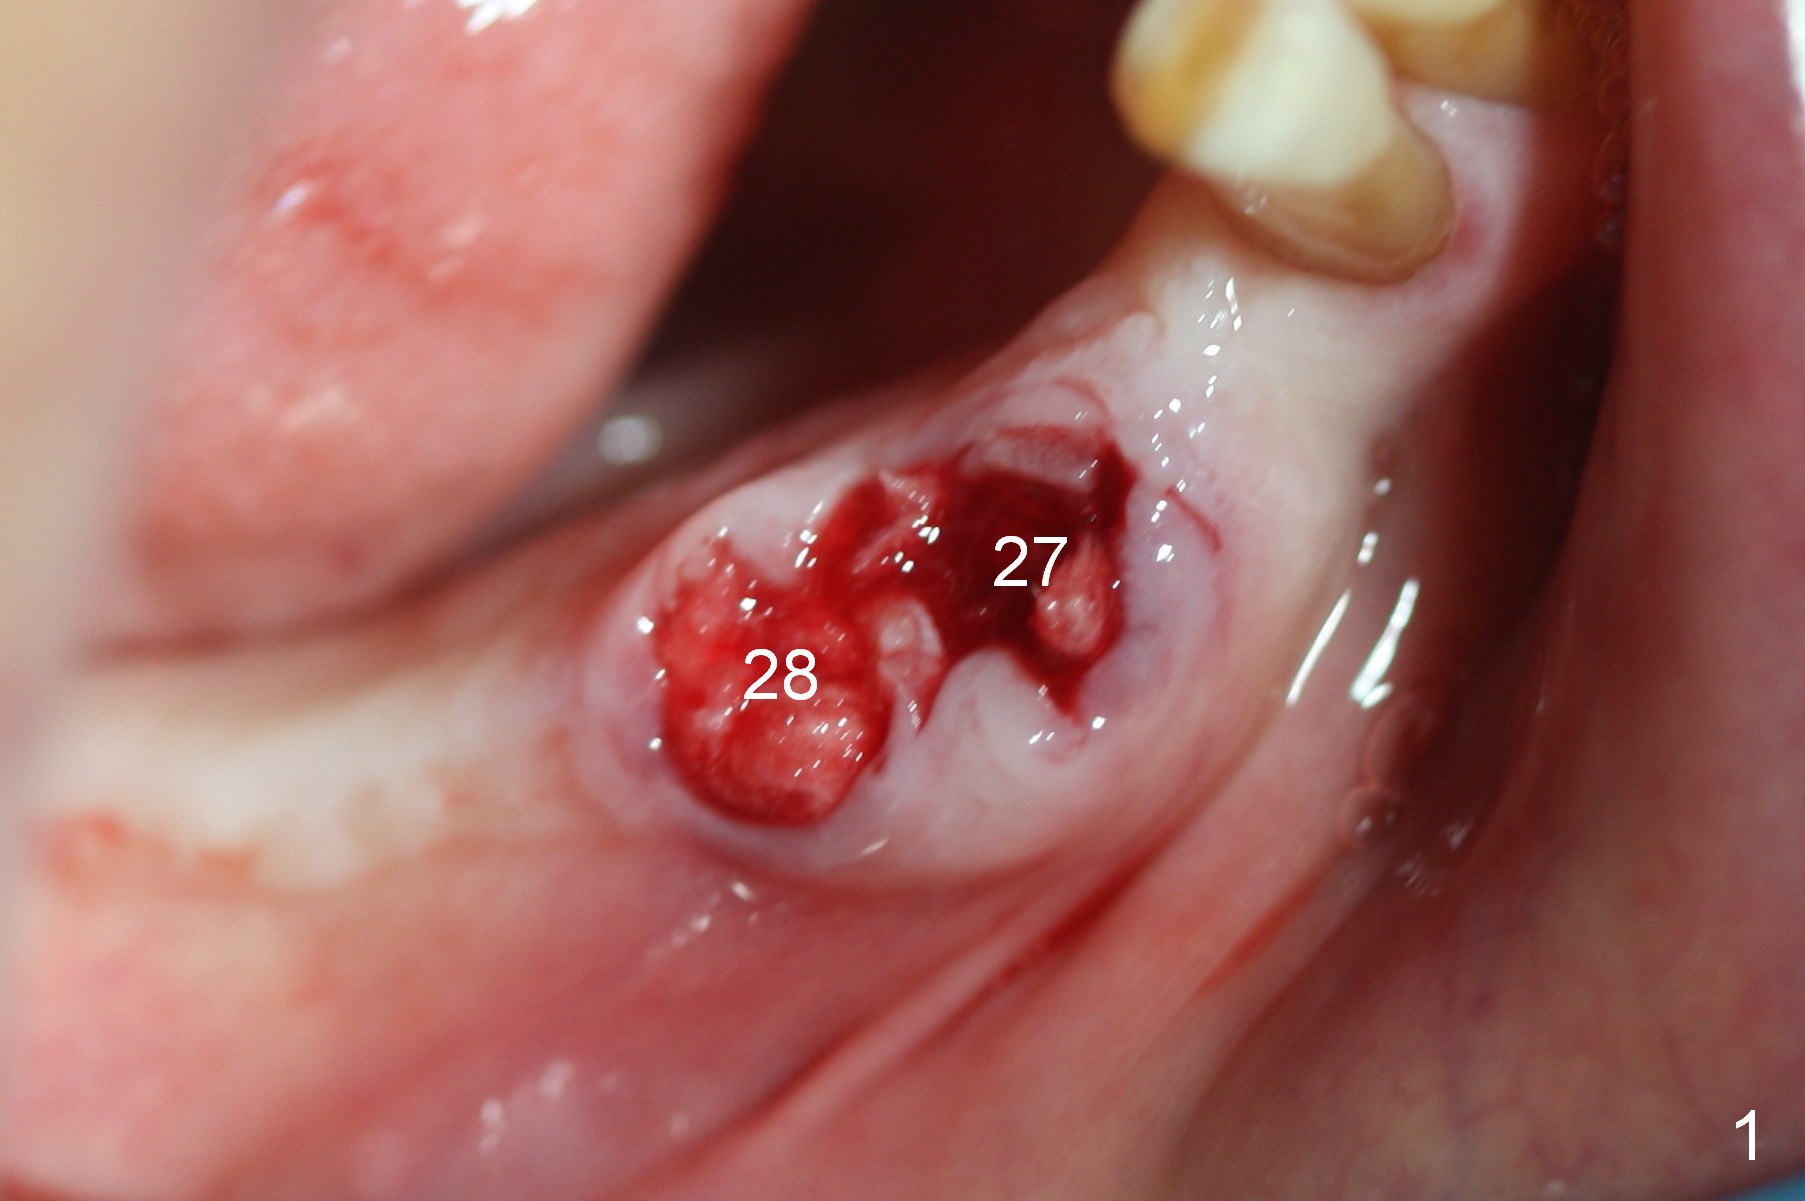

A 86-year-old man returns to office for the lower right quadrant reconstruction with implants. In addition to the immediate ones at the sites of #27 and 28 (Fig.1), how many and where else? The patient reveals that he does not plan to get an implant at the site of #3 (Fig.2). Therefore there is no need for an implant at #30. Preop CT shows that bone width is compromised at #26. So the 3rd site will be #29 (Fig.3,4). All of the 3 implants (4.5x14 mm, 4.5x12, and 4.1x12 mm) achieve primary stability (»55 Ncm). An immediate provisional could be provided, but it seems difficult to close the buccal (Fig.5 B) gaps of #27 and 28 after bone graft with the provisional. In contrast, the gingiva adapts to the implant at #29 well (Fig.6 B). Perio dressing is applied to the abutments (Fig. 7: #27-29), the edentulous space at #26 and the neighboring teeth (#23,24). It would be ideal to apply a non-resorbable membrane to the buccal opening at #27,28 (Fig.8 white line) prior to perio dressing placement. In case of dislodgement of the latter, the membrane is able to keep bone graft in place.

Eight days postop, the most anterior portion of the perio dressing is dislodged; the rest is stable (Fig.9). Since the patient has difficulty in coming to office, the perio dressing is removed. While the buccal gap of #27 has closed apparently (Fig.10 ^), that of #28 not (*). To prevent irritation from the abutments, a splinted provisional is fabricated (Fig.11 P). Perio dressing should have been re-applied buccal to the gap at the site of #28 or preferably the original perio dressing should have not been removed prematurely.